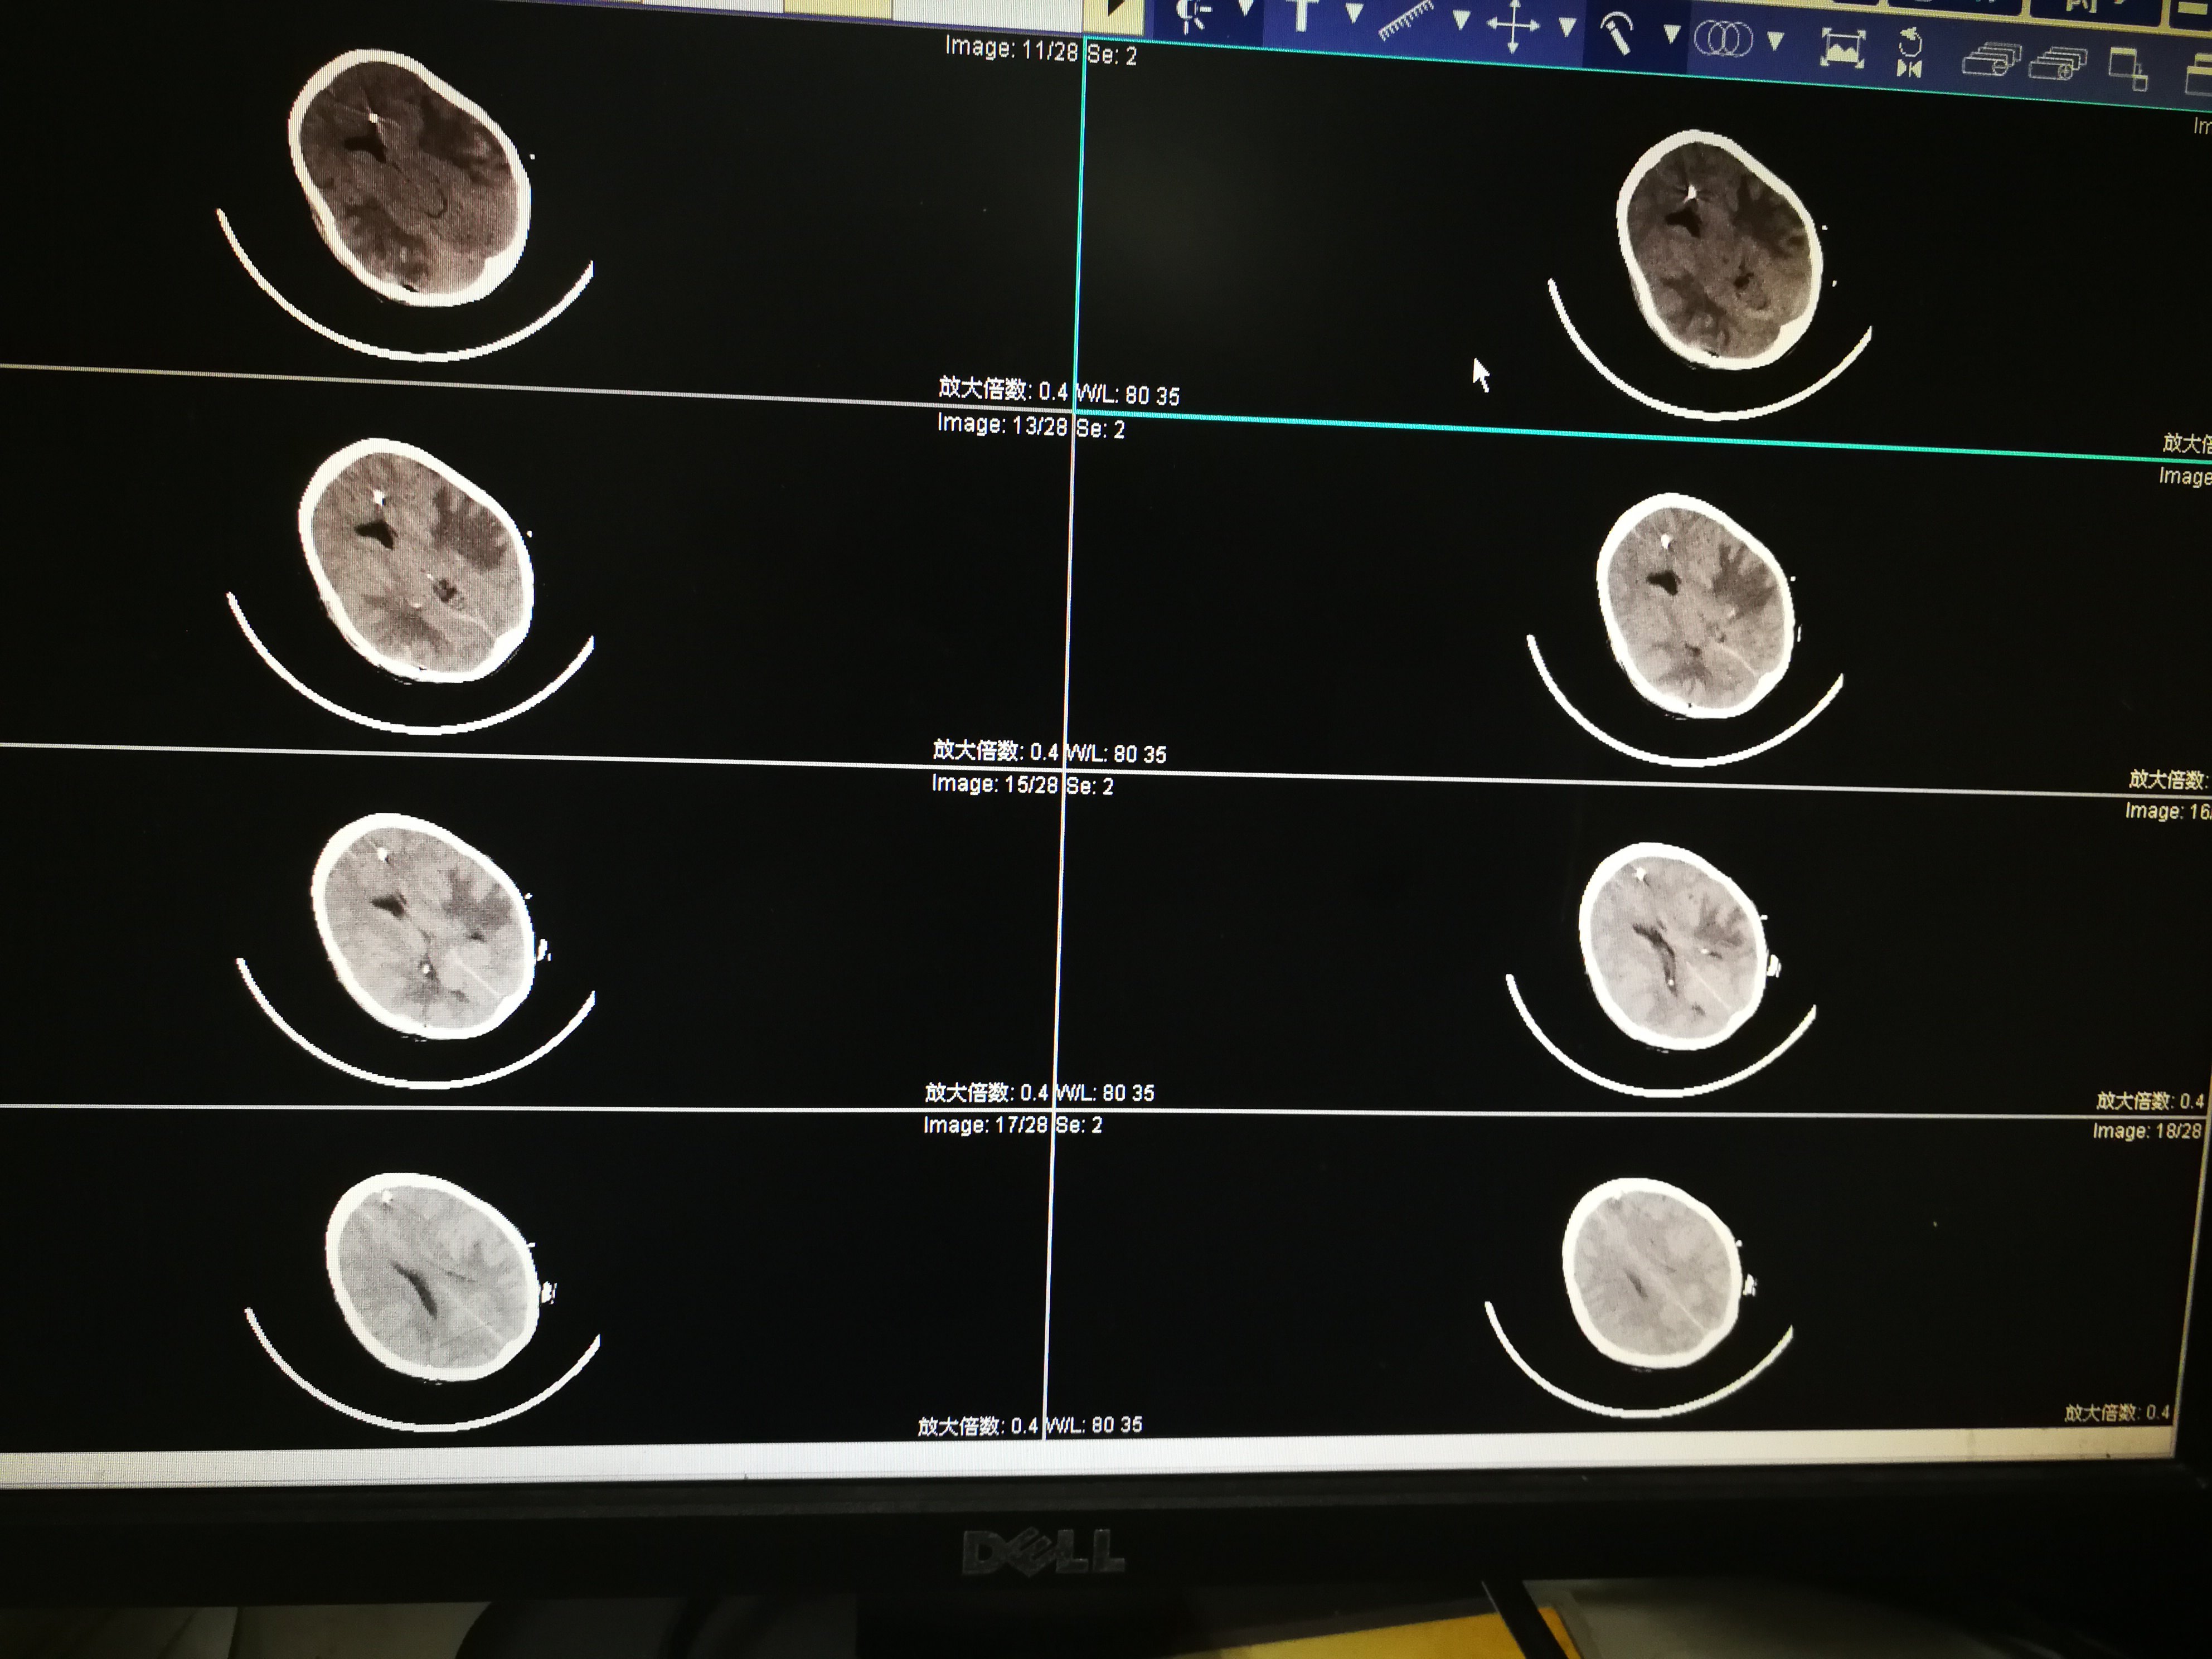

脑外伤术后颅内压监测,让我们对疾病的判断从经验走向循 - 好大夫在线

图片尺寸3968x2976